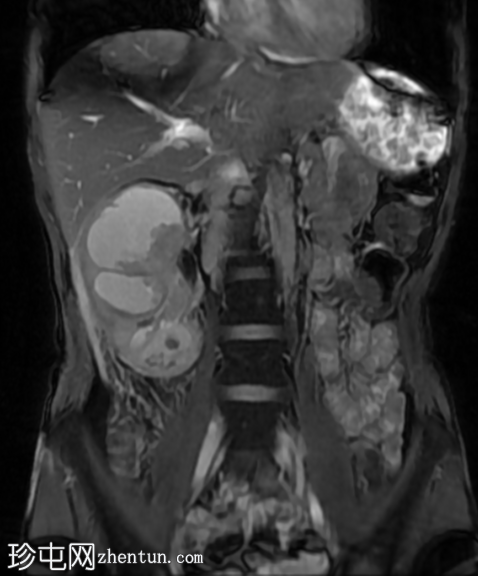

MRI

4.png

冠状位

T2加权像

再次观察到上述肾前部外生性病变,其实性成分在T1加权像上呈等高信号,在T2加权像上呈低信号,伴有碎片扩散受限和低ADC值(化脓性物质)。囊性成分内部可见液-碎片/脓液界面。可见内部低信号结石。可见肾周模糊影。该病变压迫并可能侵犯右肾盂,导致中度肾积水。

病灶不规则的低信号,以及液-液界面伴有碎屑(可能为化脓性物质)扩散受限和肾周模糊,再次高度提示炎症性病变(黄色肉芽肿性肾盂肾炎,XGP),而非可能性较小的肿瘤。

左肾萎缩,体积较小,内含多发低信号结石。